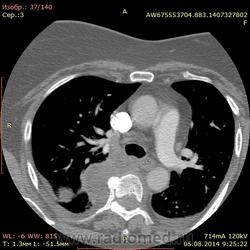

Для коллеги Makcimalist.( обещанное) Случай падения с высоты 2-3м, удар головой об асфальто-бетонное покрытие, рабочий 1982г., голова по КТ как огурчик (холодно - подшлемник, шапка + ЧУДО! каска строителя!). Пострадала шея, подвывих( нет нейросимптомов, руки-ноги - сам пришел с начальником), есть переломы - увы.... . Причем один из них обещанный - продольный тела позвонка. На обычных рентгенограммах- только подвывих.( снимков обычных не могу показать) На снимках смотрел лично, если сильно придираться - неровность верхней пластинки С3. Переломы дужек само - собой.

. Причем один из них обещанный - продольный тела позвонка. На обычных рентгенограммах- только подвывих.( снимков обычных не могу показать) На снимках смотрел лично, если сильно придираться - неровность верхней пластинки С3. Переломы дужек само - собой.

Спасибо за случай! Разрезали, всё-таки, позвонок!) То есть пациент разрезал его сам, Вам (и себе) в копилку мудрости немного помог.) Насчёт того случая (с грудным отделом) - там всё же замыкательная пластинка заметно просела, не то что здесь на сагитталах - даже ни чуточку. Коллега, как Вы считаете, отчего такой разрезающий перелом маловероятен (предположительно) в отделе другом (например, том же грудном)?.. Даже при падении вниз головой?

Коллега, я понимаю (мне чудится, что понимаю ) Вы про мышечно-связочный т.н. "корсет" грудного отдела. Имелись и грудного и поясничного продольные"расколы" без компресии!, ищу ...(около 5000 в год КТ, сортирую по КТ позвоночника, найду - выложу.)